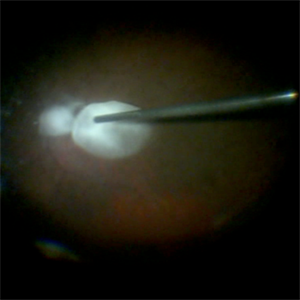

Staining-the-vitreous

This is an example of staining the posterior hyaloid in an eye with no PVD with triamcinolone actinide to assist with inducing a PVD prior to repairing the macular hole.

Condition/keywords: macular hole, PVD, triamcinolone, triescence